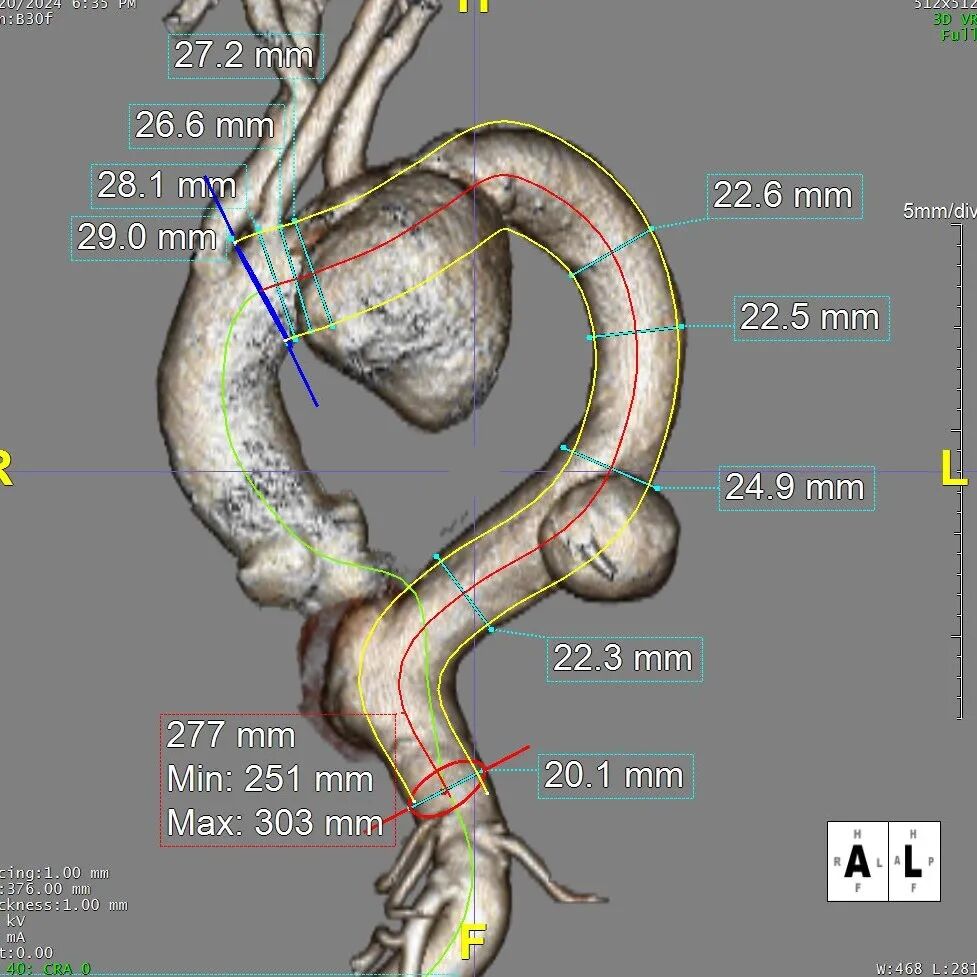

术前CTA详解

术前CTA.

术前3D重建

巨大胸主动脉瘤,直径70mm

病变累及LCCA附近,小弯侧锚定区长度11mm,非常极限

降主动脉瘤远端锚定区长度

INA后缘至CA上缘长度

考虑患者整体身体状况较差,选择腋动脉-左颈总动脉和腋动脉-左锁骨下动脉人工血管搭桥术,大支架锚定于INA后缘。由于病变累及至LCCA,INA后缘小弯侧锚定区极限11mm,为获得足够的健康锚定区,需要极其精准的定位,遂选择GORE® TAG® 可主动调控胸主动脉覆膜支架(以下简称“CADS”)。

结合近远端血管直径及锚定区长度选择:近端戈尔CADS TGM343420+远端唯强DM-TC-3024200。